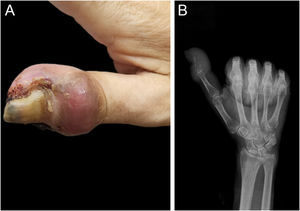

Dermatological examination revealed a firm, purplish-red swelling encompassing the distal phalanx, accompanied by erosion of the nail folds, thickening of the nail plate, discoloration, and irregular nail morphology (Fig. 1A). Radiographs revealed marked osteolytic destruction and loss of structural integrity in the distal phalanx (Fig. 1B).

(A) In the distal phalanx of the right thumb, there was a purplish-red swelling encircling the finger, accompanied by erosions of the nail folds, thickening of the nail plate, discoloration, and morphological irregularities. (B) Radiographic imaging revealed extensive bone destruction and a loss of the anatomical integrity of the distal phalanx.